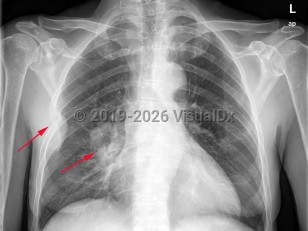

Greater than 95% of lung cancers can be categorized as either small cell lung cancer (SCLC) or non-small cell lung cancer (NSCLC), with adenocarcinoma and squamous cell carcinoma being the most common NSCLC. Carcinoid tumors and mesothelioma may also arise in the lung but are less common. The lungs are also a common site of metastatic cancer.

Some tumors may be associated with multiple metastases to the lung, which can cause rapid onset of pulmonary hypertension. Sometimes, cancer may invade the esophagus and cause a bronchoesophageal fistula. Lung cancer is a common cause of obstruction of the superior vena cava and superior vena cava syndrome. Cushing syndrome is a common paraneoplastic association.